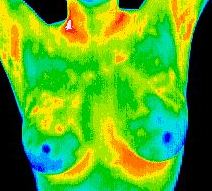

Darstellung integrativer Verfahren ohne Röntgenstrahlen, die gutartige und bösartige Veränderungen der Brust unterscheiden helfen.

Die Thermographie ist eine hochtechnologische Methode, die Wärmefelder bildlich darstellen kann und sich daher besonders gut für die Ermittlung von Entzündungen im Körper eignet.

Die Thermographie kann zudem als effektive Alternative zur gefährlichen Mammographie bei der Aufspürung von verdächtigen Verhärtungen oder Schmerzen in der Brust, um die Patientin zum Frauenarzt:in zur Abklärung durch Ultraschall oder falls notwendig zur Mammographie zu überweisen.

Alexander Mostovoy ist ein homöopathischer Arzt mit einer vielbeschäftigten Praxis in Toronto, die auf die Gesundheit von Frauen spezialisiert ist. Er ist ein zertifizierter klinischer Thermograf. Sein Fachwissen liegt in der natürlichen Behandlung von Wechseljahren, Krankheiten und Brustkrebsprävention. Er ist auch Klinikleiter einer Klinik für medizinische Thermografie, einer der wenigen Kliniken im Land, die kanadischen Frauen medizinische Infrarot-Thermografie anbieten. Die medizinische Infrarot-Thermografie ist ein strahlungsfreies, sicheres und schmerzloses Verfahren zur Früherkennung von Brusterkrankungen. In Verbindung mit der Mammographie und anderen derzeit verfügbaren Tests kann die Früherkennung von Brustkrebs bis zu 90 % betragen. Die Infrarot-Brustthermografie ist eine Methode zur frühesten Erkennung von Brustanomalien, die derzeit bekannt ist.